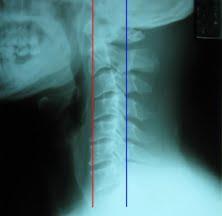

교통 사고시 발생한 채찍 손상으로 경추 주변의 근육이 손상되어서 발생하는 통증이 가장 많지만 그 손상의 정도가 심각할 경우에는 경추의 추체와 추체를 연결하여 고정하는 인대가 손상되어 경추의 불안정을 초래하게 되기도 합니다. 경추의 불안정성을 평가하는 방법은 위와 같이 엑스레이를 찍어보는 것 입니다.

이러한 긴장은 목의 경추만곡(목은 약간의 C자 모양의 커브를 이루어야 함)이 감소되어 일자목이 형성되거나 더 지나치게 되면 후만이라고 하여 C자모양이 역전되는 현상이 일어납니다.

일자목과 교통사고 후유증과의 관련성은 연구자마다 상반된 결과를 보입니다. 그러나 채찍손상으로 근육이나 인대의 손상 또는 디스크가 발생되어 근육이 긴장되면 일자목의 발생 가능성은 매우 높아집니다.

다만, 이 일자목의 정도가 심하다고 해서 교통사고 후유증의 예후가 나쁘다고 일방적으로 말하기는 어려운 것 같습니다.